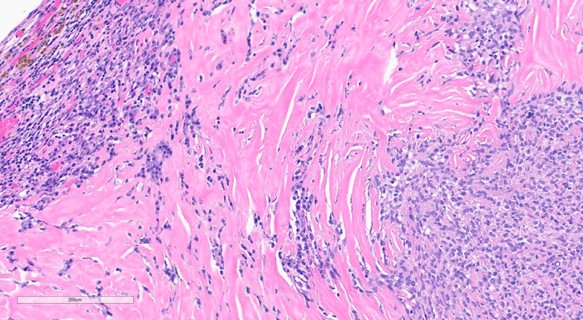

Representative Histology / IHC: